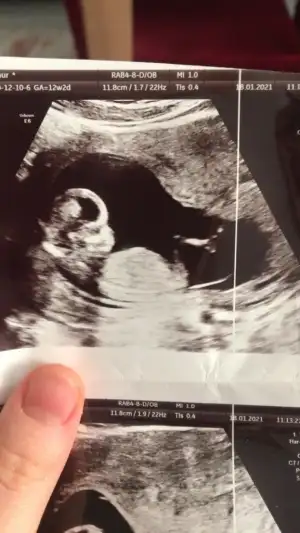

Erkek görünüyorAmin canım hepimizin12 haftalık usg resmi benimde

Bakalım bu hafta gidicem büyük ihtimal söyler heraldeErkek görünüyor

Net değil nubu emin olamadim başka USG varsa paylaşın sanki kız ama emin değilimMerhaba 12 haftalık tahmin edebilir misiniz![]()